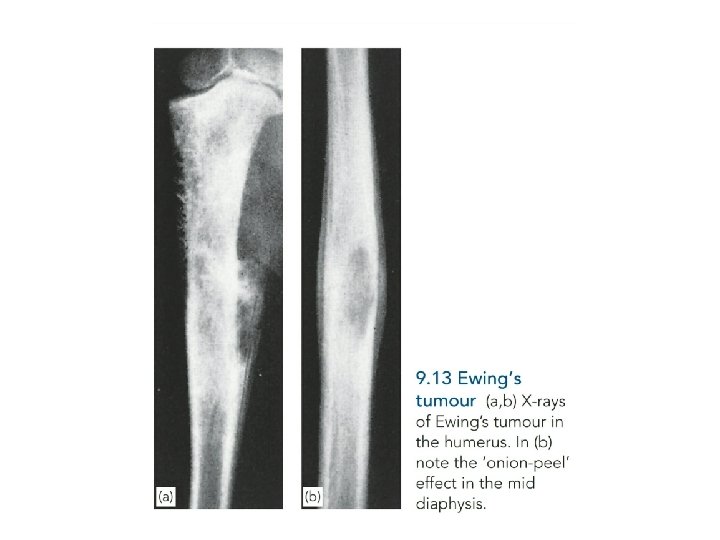

Ewing’s Sarcoma • Ewing’s sarcoma is believed to arise from endothelial cells in the bone marrow. • Incidence: peak at 10– 15 years. • Primary tumor: often diaphyses of long bones (particularly femur, tibia, fibula, and humerus) and bones of the pelvis. • Metastasis: lungs, skeletal system, bone marrow

• The patient presents with pain – often throbbing in character – and swelling. Generalized illness and pyrexia, together with a warm, tender swelling and a raised ESR, may suggest a diagnosis of osteomyelitis.